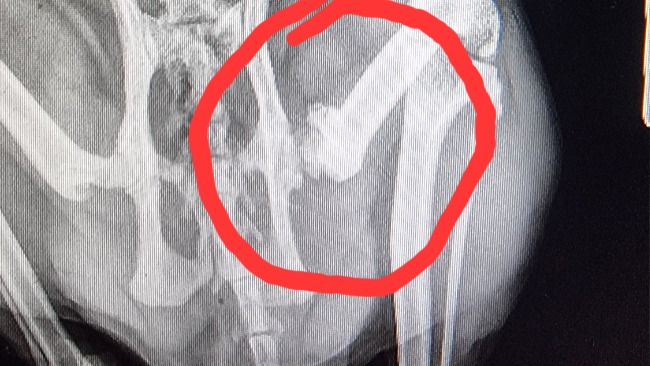

Dostał antybiotyk,steryd I miałyśmy nadzieję że to podziała . Ale jak robił po kropelce tak na drugi dzień nie robił już wcale tylko kucał i nie mógł się załatwić. Ponowna wizyta u naszej Dorotki i okazało się że stało się to co najgorsze, zatkał się . Musiał mieć podaną lekką narkozę aby można było go odetkać , prawie dwie godziny trwało zanim udało się przebić do pęcherza,ale się udało więc była nadzieja że będzie tylko lepiej. Przy tym wszystkim kochana kocina straciła zupełnie apetyt,musiał dostawać kroplówkę i tabletkę na apetyt ale niestety wymiotował to ci udało mu się zjeść. Ale na ty to się nie skończyło biedactwo na trzeci dzień ponownie miał problem z sikaniem. Wizyta u lekarza i ponowne zatkanie cewki. Kolejna godzina przepychania i decyzja o wszyciu cewnika . Tak biedactwo chodziło dwa dni tylko zmieniałam mu pampersy i podkłady a że był w kołnierzu to utrudniało mu też jedzenie. UrinoVet Cat, antybiotyk , nos-pa,kroplówka ,omnic na rozszerzenie cewki i gabapentyna na wyciszenie zaczęły pomagać. Po dwóch dniach miał wyjęty jednak cewnik i na szczęście to pomogło bo chociaż z krwią ale sikał wszędzie gdzie popadło . Myślałam że to już koniec niespodzianek ale niestety. Zulu po gabapentynie którą przyjmował stał się bardzo spokojny i trochę kołowaty i tego felernego dnia chciał wskoczyć na 30 centymetrowe pudełko Felixa a że był słaby to nie dał rady tylko osunął się na podłogę. Wieczorem zaczął kuleć na prawą tylną łapkę ale myślałam że może sobie coś nadwyręża lecz na drugi dzień już nie mógł stawać na tej łapce tylko trzymał ją w górze i widać że go boli. Wizyta u lekarza i decyzja o zrobieniu RTG no i wyszło że ma złamaną główkę kości udowej przy panewce.

Lekarz powiedział że potrzebna jej niestety operacja aby mógł wogóle chodzić. Załamałam się, jak to możliwe. Przypomniało mi się że po jednej z adopcji zabrałam go z niesprawną właśnie tą łapką i wtedy to było pęknięcie, gdzie pani nie wiedziała dlaczego to się stało bo tylko mu lekko nadepnęła na łapkę, ale lekarz nie kazał nic robić że to się zrośnie . I widocznie teraz, kiedy był osłabiony i nie mógł się obronić przed upadkiem z tego cholernego pudełka to widi żnie osłabiony a kość po tym pęknięciu po prostu się złamała.